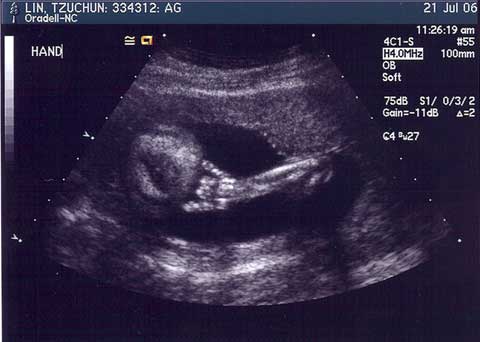

Dec. 13, 2006 - Welcome, little one...

Introducing Devon Cheng, born December 12, 2006. 6 pounds, 14.4 ounces and 19.5 inches long. All fingers and toes and other extremity accounted for. =)

Jul. 24, 2006 - No time wasted

Well this recent development certainly came as a surprise. I don't think it's sunk in 100% quite yet (that probably won't be until after birth) but it's getting there. As of this most recent ultrasound, the kid is 19 weeks and 4 days old (well, a full 20 weeks now). And it's a boy. At least we're pretty sure that it's a boy. I guess we'll double-check a few months down the line during the next ultrasound. ;-p Oh, and his due date is around the middle of December. Erin's hoping that he'll come earlier rather than later cause she'd rather have a Sagittarius baby instead of a Capricorn (no disrepect to you Capricorns out there).

Hand

This pic can mean one of 3 things:

1. He's going to be a rocker when he grows up.

2. He's part Hawaiian.

3. Our phone bills are going to skyrocket.

Anyway, this will have to do for now. No doubt my future blog entries will be baby-oriented just a little bit. ;-) You have been warned.